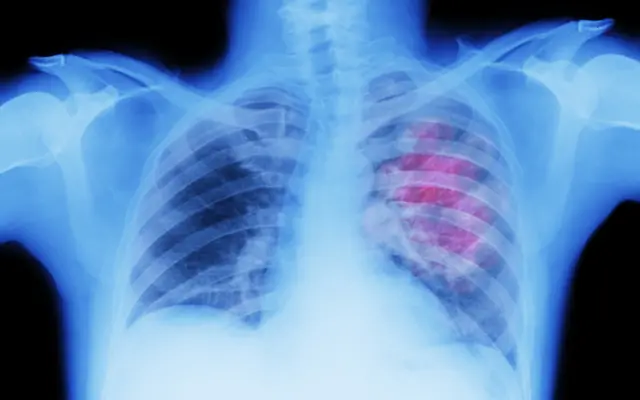

Toser sangre podría ser un signo de cáncer de pulmón.

Una tos persistente puede que sea un signo de cáncer de pulmón.